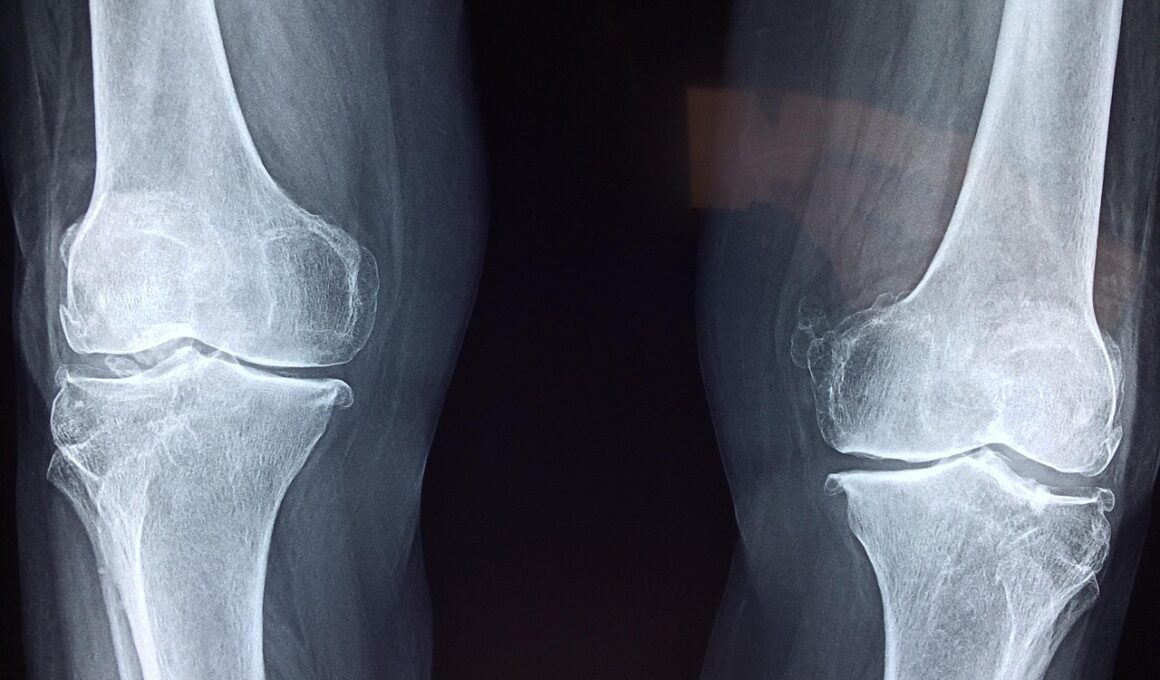

As our world becomes increasingly digital, more employees find themselves confined to their desks. While desk jobs often come with several advantages, prolonged sitting poses significant risks to our joint health. The joints, particularly in the lower body, experience reduced mobility and flexibility over time. This sedentary lifestyle can lead to stiffness, discomfort, and other joint-related issues. Regular movement is crucial to keep joint tissues hydrated and nourished. Furthermore, poor posture while sitting can exacerbate these problems, causing additional strain on the shoulder, back, and neck joints. Issues like arthritis can become more prominent when joints are not adequately utilized. It is essential, therefore, to devise strategies to mitigate these risks. Encouraging employees to stand or walk during calls, adopting ergonomic office furniture, and reminding them to stretch periodically can significantly improve their daily routine. Simple changes in behavior and work environment can lead to a more active lifestyle, thereby enhancing joint health over time. Ultimately, awareness of the impact of desk jobs on joints is the first step towards a healthier work culture that prioritizes well-being.

Prolonged sitting has been linked to various health complications beyond joint issues, potentially leading to serious medical conditions. In addition to affecting joint flexibility, it can also contribute to weight gain, cardiovascular diseases, and even diabetes. During sitting, our muscles tend to be inactive, slowing down metabolism and leading to a higher likelihood of obesity. The decreased blood flow to the joints resulting from long periods of sitting can cause inflammation, increasing the risk of conditions such as bursitis and tendinitis. Employees often report discomfort or pain in their hips, knees, and lower back from sedentary behavior, which can diminish their productivity and hinder overall job satisfaction. Introduction of standing desks, adjusted chair heights, and designated walking breaks within office hours can drastically improve workplace ergonomics and, consequently, joint health. Companies should prioritize strategies to minimize these risks by fostering an environment that encourages movement. Team challenges, walking meetings, and lunchtime yoga can serve as engaging solutions to promote joint-friendly habits during the workday. An emphasis on wellness can subsequently boost morale, enhancing both physical and mental well-being in the workplace.